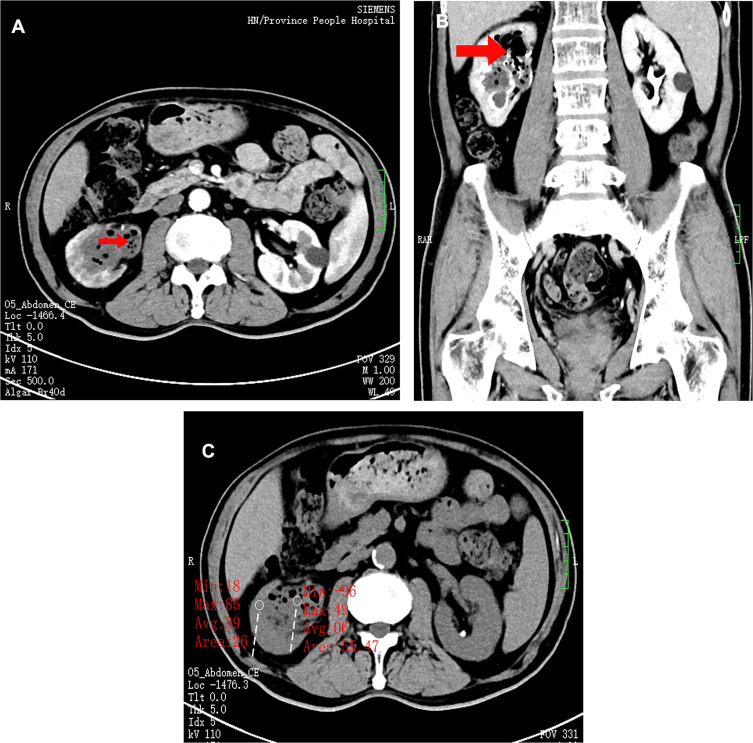

Figure 1.

(A) In the bilateral kidneys in the contrast-enhanced CT window, the side marked with red represents the right renal pelvis, and the pneumopelvic shadow in the renal pelvan be seen at the red arrow, while the dilatation of the left renal pelvis is not obvious on the right side, and there is no obvious gas accumulation. (B) In contrast-enhanced CT windows in different slices, right pneumopelvic shadow is seen at the red arrow, and plenty of air and infected shadows are seen in the renal pelvis. (C) In the unenhanced CT window, the CT value of the right renal pelvis can be seen at the two red marks compared with the CT value of the infection in the renal pelvis.